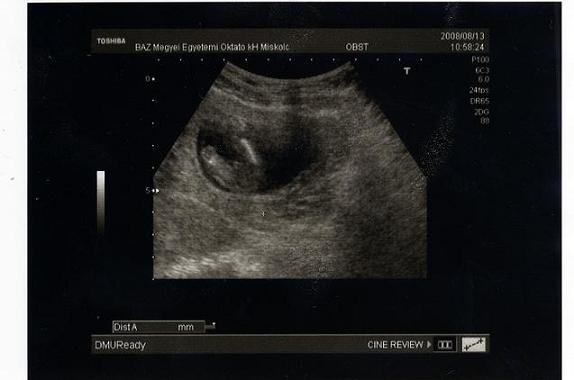

Íme a tegnapi képek.

A kakasos képet úgy képzeljétek el, hogy ülő pózban van a baba és mi alulról látjuk a fenekét. Kép Öcskös